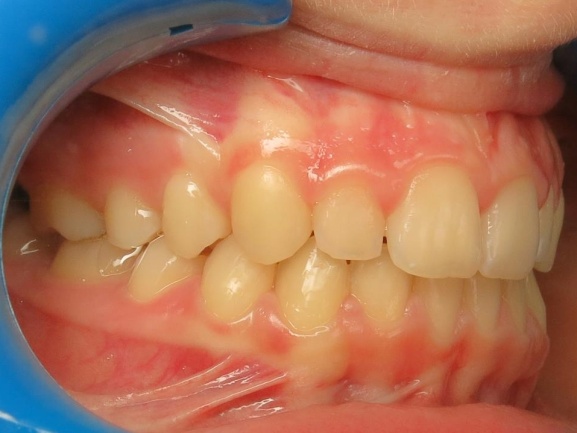

3 - Phase 2 : traitement orthodontique- alignement des dents et occlusion

Le traitement a d’abord consisté à corriger le décalage entre les bases osseuses des mâchoires par une phase orthopédique. Une fois cet équilibre rétabli, un appareil multiattaches a été mis en place pour aligner les dents sur des bases désormais bien positionnées. La dernière étape a permis de peaufiner les contacts entre les dents afin d’obtenir une occlusion fonctionnelle et stable.